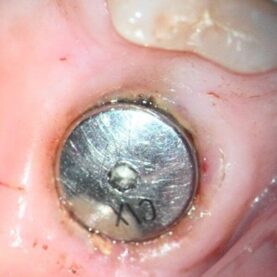

At the patients request, post clinical appointment and prior to leaving, a detailed conversation was entertained as to why this abutment had failed in such a short time frame. The patient has not needed and therefore has had relatively little dental work to date, so the extraction of #30, implant placement and restoration with failure occurring so quickly, was troubling to her. As I evaluate all the implant abutment fractures in regard to duration in function, location of the fractured component, and the amount of fractured abutment material and type, this case was no exception. While it was no surprise to see another Ankylos abutment fracture on the schedule in a single tooth molar application, the very short time it took to fracture was interesting. The intake form listed this abutment as an Atlantis abutment, but it quickly was apparent this was not the case. The first clue was that tapping progressed rather quickly and while the threads were not deep, a slight eccentricity in the bore allowed for enough thread depth for successful distraction. Once the abutment fragment was recovered, the apical portion of the recovered abutment has a notched geometry as in the top of a castle. This can be appreciated in the above photo of the abutment fragment on the distractor. Ankylos and Atlantis abutments do not have this as the end of their abutments are not notched. This notching is due to a larger diameter through bore which invades the internal wall thickness in the indexing spline areas. While not Ankylos or Atlantis it is consistent for a non-OEM Glidewell abutment and possibly other non-OEM abutments as well. The following photo shows the recovered abutment fragment on the right and an intact Glidewell abutment on the left. Both are on a 1.78mm gage pin which goes completely through the Glidewell abutment and goes into the recovered abutment fragment until it hit a distorted area, secondary to the threading process. The stock Ankylos abutment has a through bore of 1.11mm vs. these at 1.78mm. So, you might say, so what? The problem is the Ankylos abutment has a maximum surface area of just 3.941 mm sq. and is ripe for fracture in this area. For comparison, a Dentsply Astra Tech EV 4.8mm implant and abutment has 9.96 sq.mm. With this Glidewell abutment, the area is reduced to 2.421sq. mm. I have never measured one this small previously. The smallest before this one was the Neodent CM interface, which is a copy of Ankylos for all practical purposes, and also has an enlarged through bore but at 1.51 mm sq. which nets out 3.118 sq.mm. These abutments also break at an accelerated rate. I believe the data is irrefutable. It might be argued this is the circuit breaker in the system to protect against implant fracture. Unfortunately, the analogy is like having a 40-amp circuit with a 5-amp circuit breaker. Almost any load will prematurely shut it down needlessly. She mentioned that a night guard was suggested. While this may help if she bruxes at night if she was able to engage posterior interferences and no anterior guidance, however, it will not protect her from loading secondary to mastication. I did not see an abundance of pathway wear to suggest a significant bruxing habit, nor did I see lateral excursive interferences. The only way I see to improve the stability of this implant / abutment connection is to use a solid abutment. This abutment will get the abutment cross section up to 4.91 mm sq. While this may work for a while, and clearly better than what was in previously, she has to understand two facts. One, I have recovered many fractured solid abutments as well, possibly 20 two-piece Ankylos abutments to one solid in approximately 220 fractured Ankylos abutment cases to date but recovering a solid is significantly more difficult to do without implant damage. Therefore, by restoring with a solid abutment it does not mean fracture is off the table. Unfortunately, I don’t have a better, simpler solution for this situation as the adjacent teeth are in good shape. I have been involved with three similar cases where the patient fractured a solid abutment rather quickly and the only real solution was to replace the implant with one that has a more overall robust mechanical connection such as a 4.8 EV.